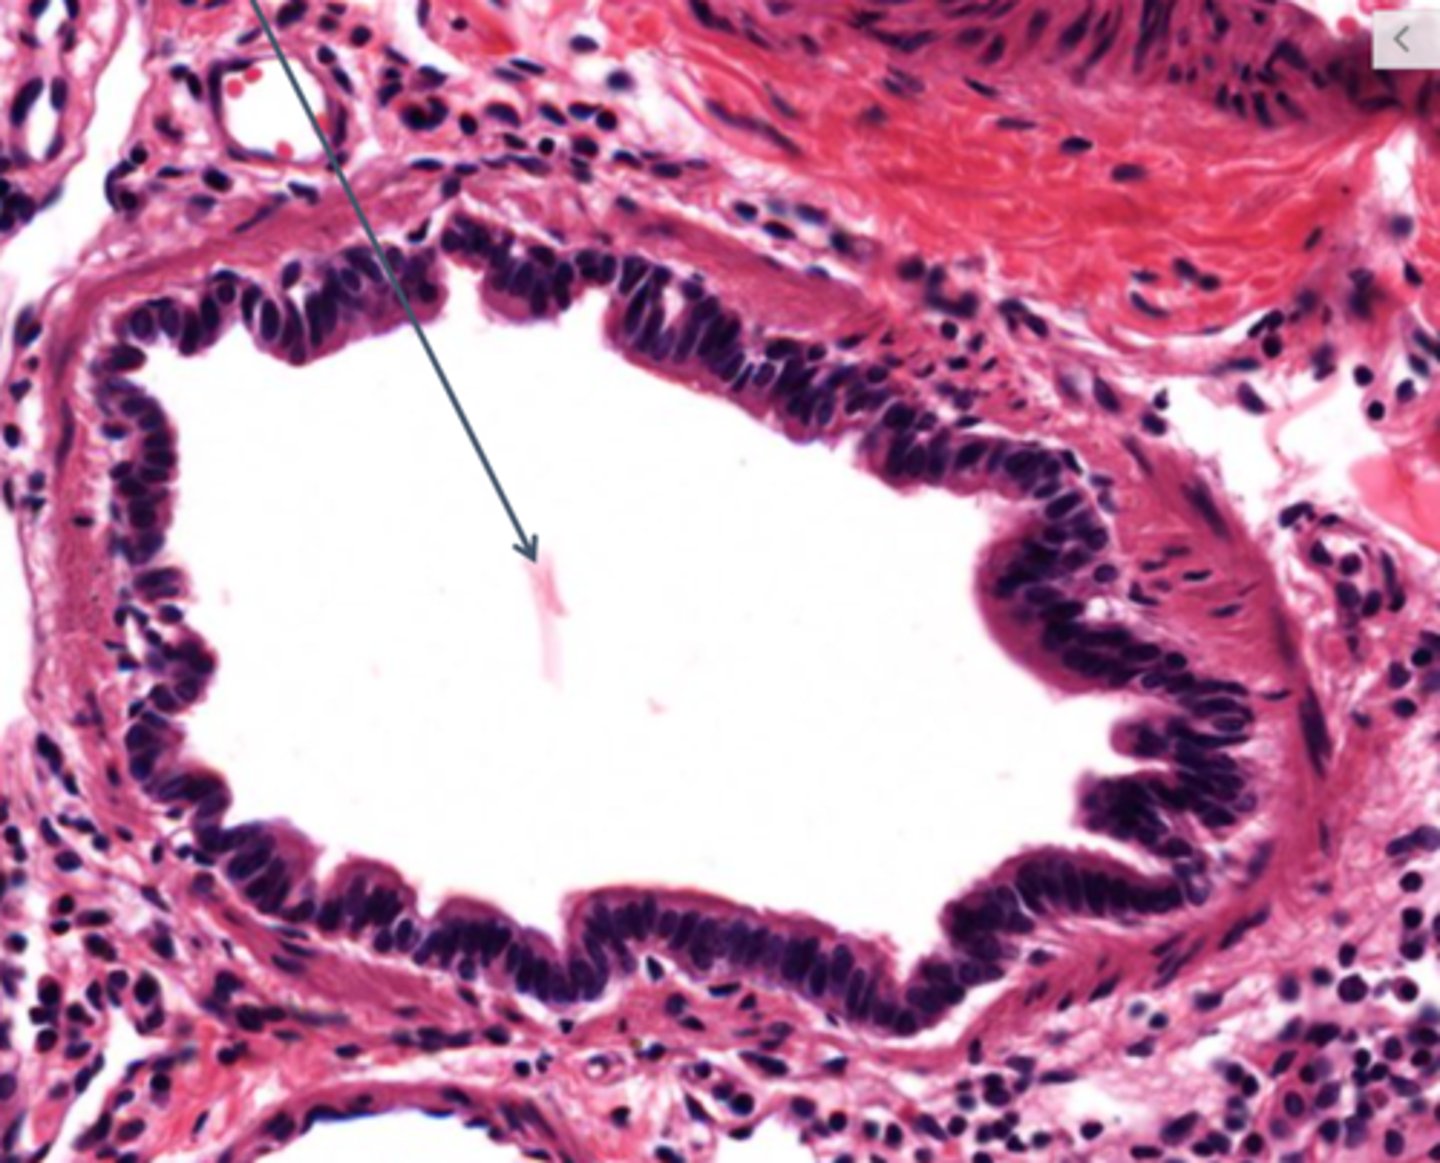

Identify the type of airway

bronchi

Identify this type of airway

bronchioles